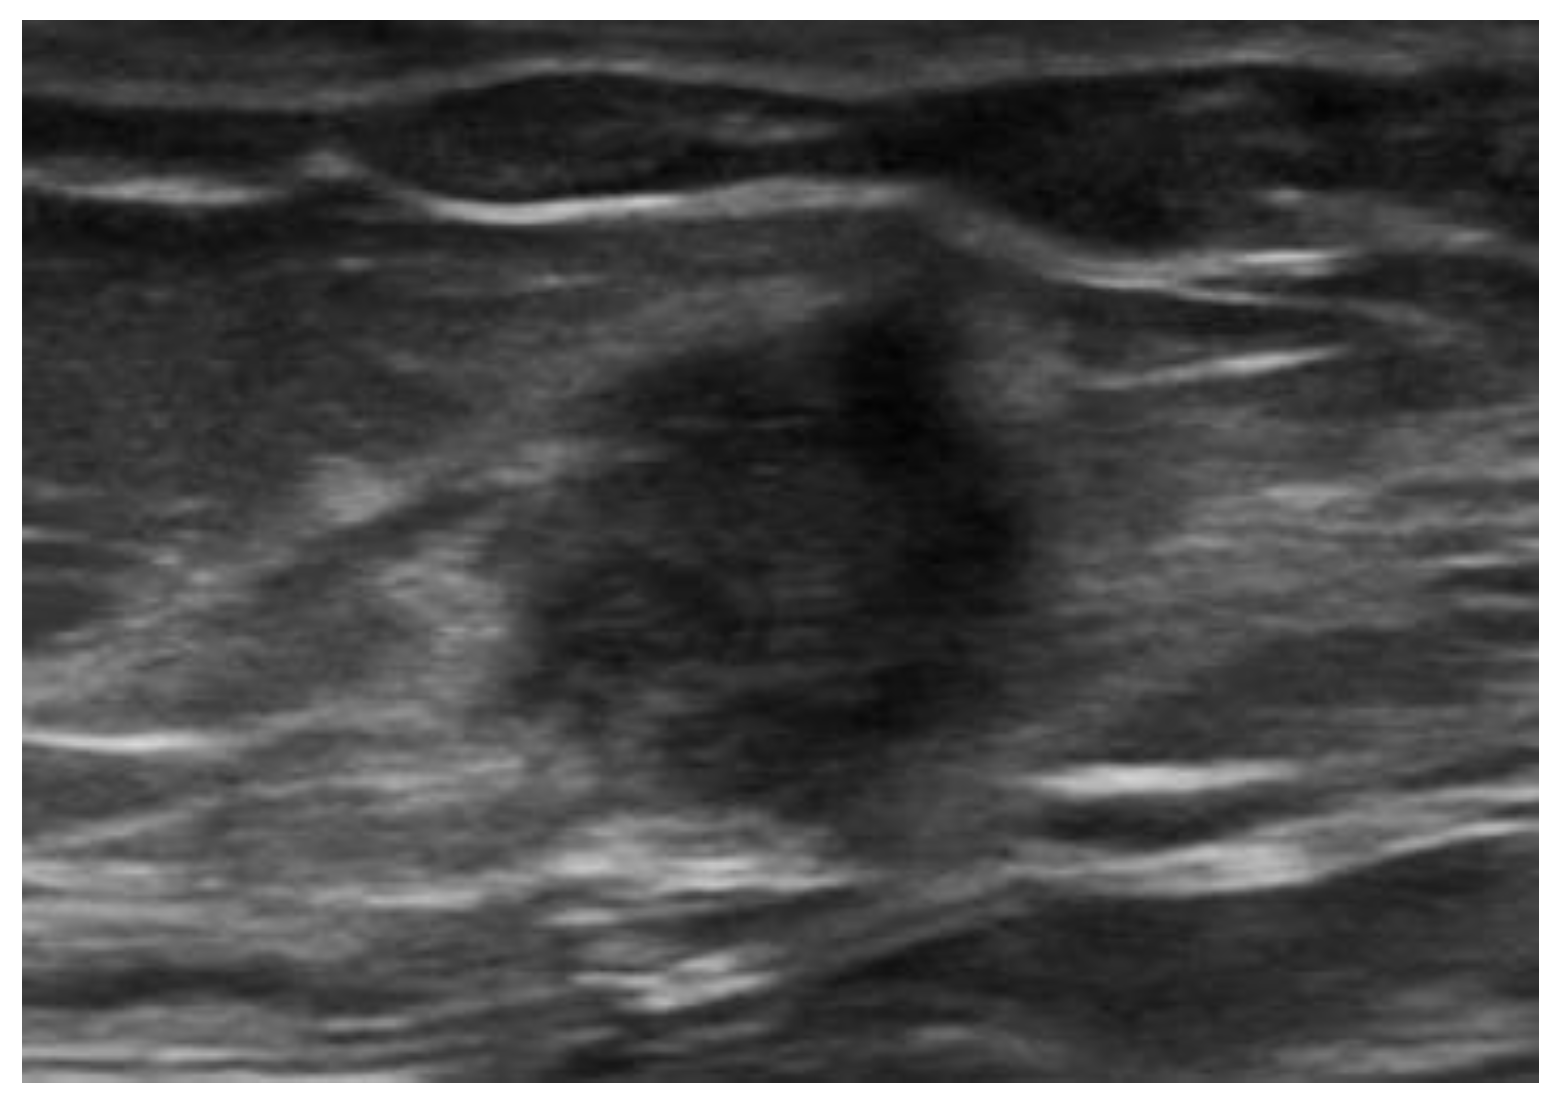

US demonstrates heterogeneously hypoechoic, round or oval-shaped nodules or masses, with scattered internal echoes, and small cystic areas [9,50,53,54], surrounded by a hyperechoic rim [55] (Figure 17).

Figure 17. Endometrioma of the abdominal wall on US: heterogeneously hypoechoic, round, or oval-shaped nodule, with scattered internal echoes.